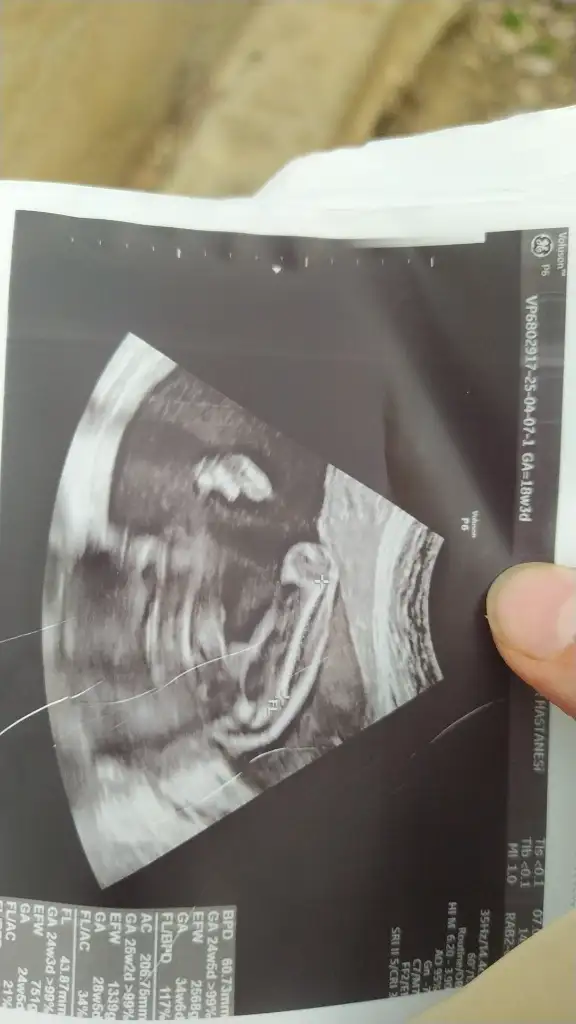

benimkine de yorum yapar mısınızz çok meraktayım en son 12.haftada gittik şu an 14+2 deyizNub teorisine göre erkek

3d görüntü ile tahmin yapamıyorumbenimkine de yorum yapar mısınızz çok meraktayım en son 12.haftada gittik şu an 14+2 deyiz

başka görüntüler var ama evde değilim çekemedim teşekkür ederim3d görüntü ile tahmin yapamıyorum